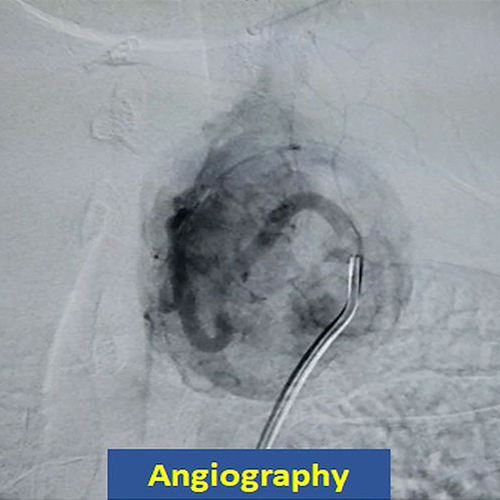

A 31 year old male with a 10cm benign solid nodule in the left thyroid lobe underwent embolization. Six months later, the volume of the nodule decreased by 90% and the appearance of the neck was practically normal.